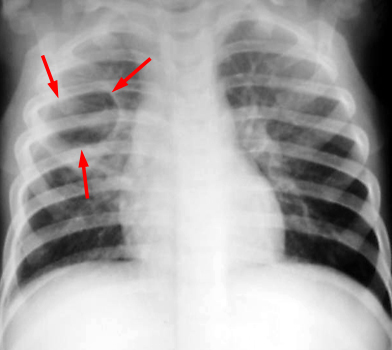

CXR a week later shows a round cyst with thin walls in the right upper lobe.